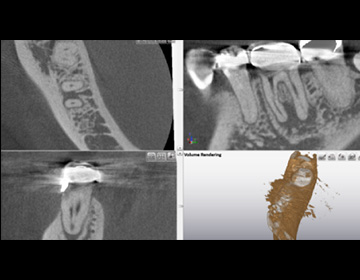

半調節性咬合器で噛み合わせ、CTで骨格のズレをチェックし治療計画を立案します。

CT撮影、模型採得(咬合器装着)、口腔内写真撮影を行います。

CT撮影、麻酔後、ラバーダム防湿を行って根管治療を開始します。